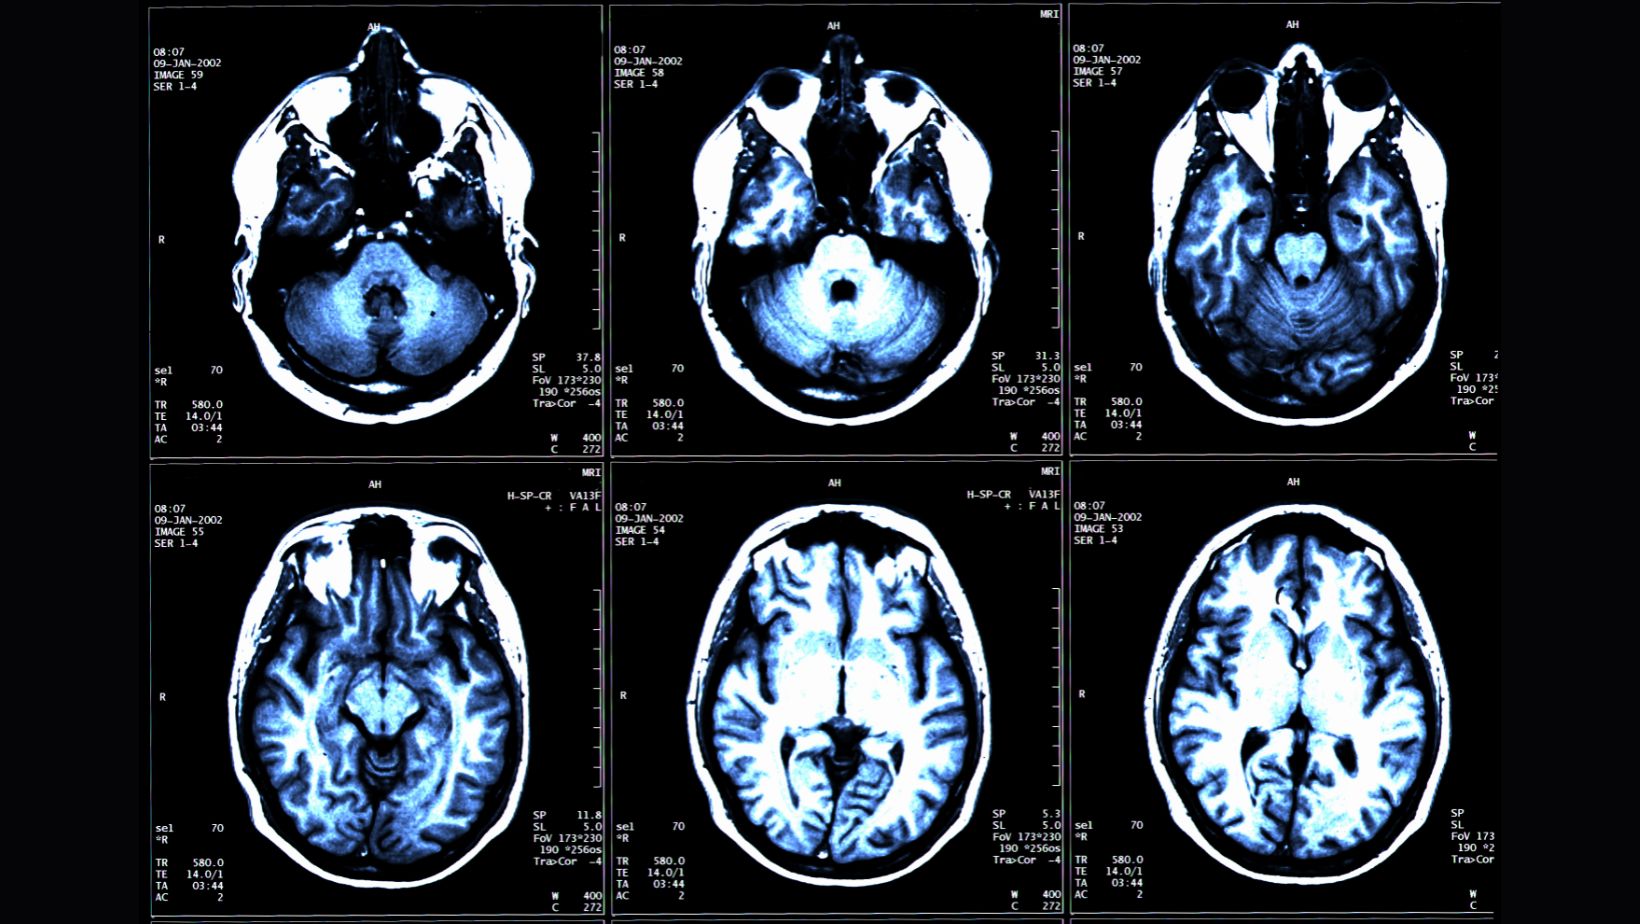

미국 워싱턴대 의대 사이러스 라지 박사팀은 25일 전신 MRI로 건강한 성인 1천100여명의 근육과 지방, 뇌 조직을 촬영하고, 총근육량과 내장지방, 피하지방, 뇌 나이 간 관계를 인공지능(AI)으로 분석한 결과 근육량이 많고 내장지방 대비 근육 비율이 낮으면 뇌 노화 속도가 느린 것으로 나타났다고 밝혔다.

연구팀은 이 연구에서 뇌의 구조적 MRI 영상의 부위별 부피를 기반으로 추정한 뇌 나이와 전신 MRI로 측정한 총근육량과 내장지방, 피하지방 사이의 연관성을 인공지능 알고리즘으로 분석했다.

이들은 4개 지역 거주자 1천164명(평균 나이 55.17세)을 대상으로 전신 MRI를 촬영하고 이를 지방과 체액, 근육 등이 다른 색으로 보이게 하는 기법과 결합해 총근육량과 내장지방 피하지방, 뇌 나이를 정량화했다.

그 결과 총근육량이 많을수록 실제 나이가 더 적고 뇌 MRI로 계산한 뇌 나이도 더 젊은 것으로 나타났다. 총근육량과 실제 나이 및 뇌 나이 간 상관계수(rp)는 각각 -0.2579와 -0.2497로 약한 연관성을 보였지만 통계적으로 유의미했다.